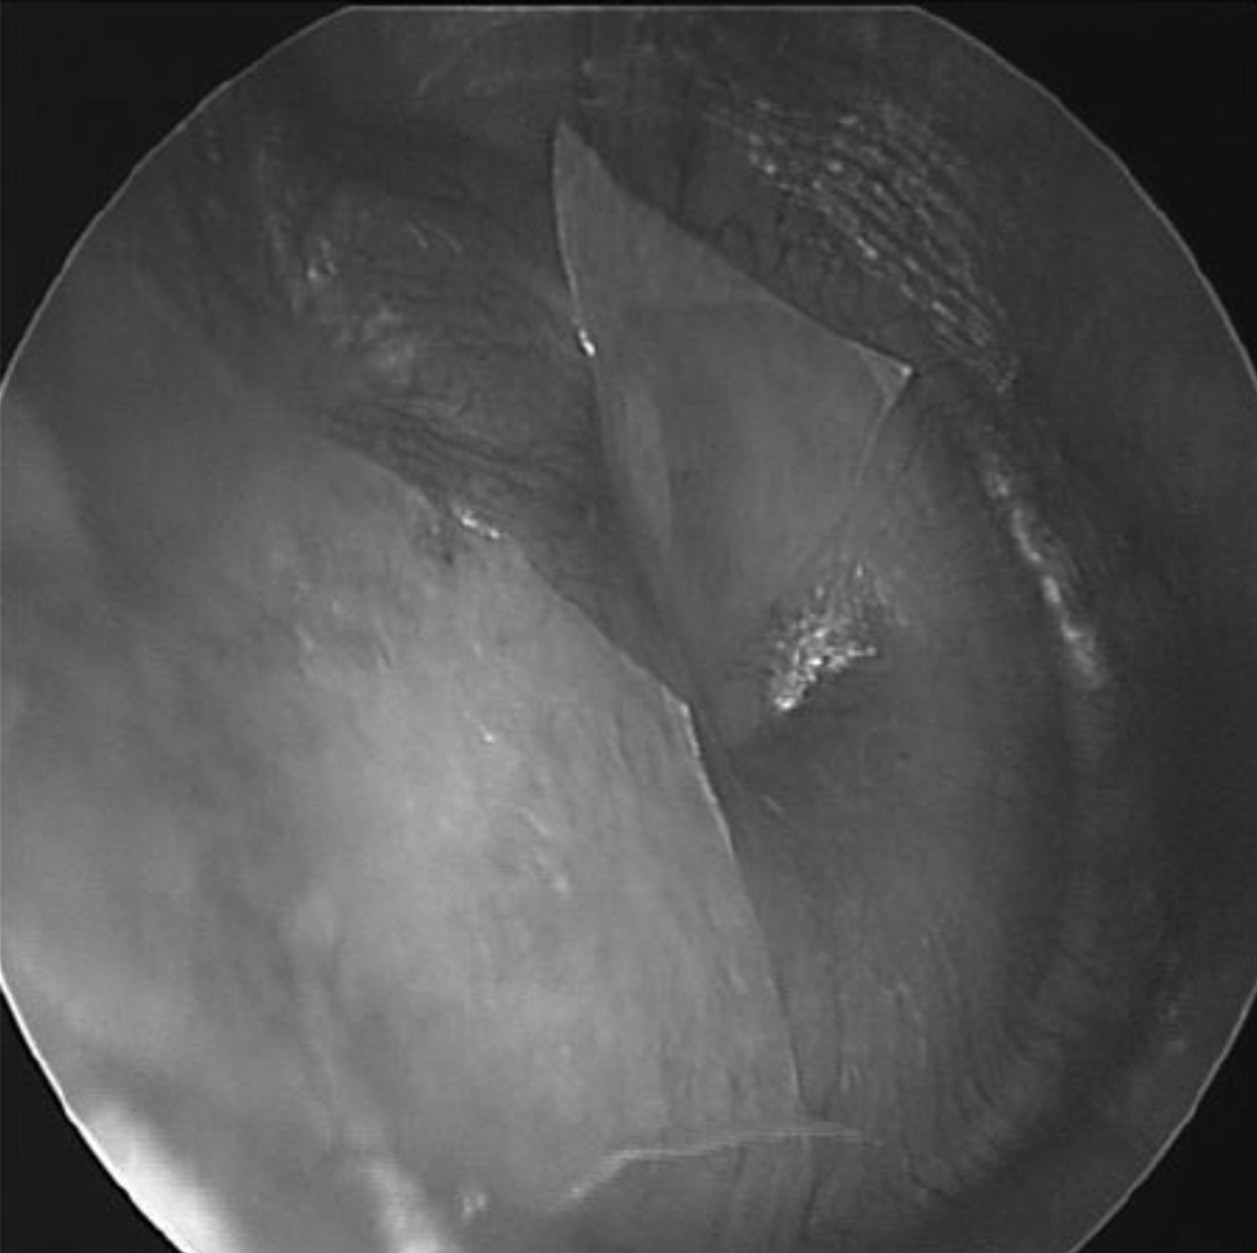

The images above show placement of paper patches on the tympanic membrane. The image on the left shows a single patch covering the inferior half of the eardrum, while the image on the right shows two patches covering the superior half. These images are from a 2014 article published by Dr. Michael Boedts, which describes the use of tympanic membrane paper patching to reduce symptoms of patulous Eustachian tube syndrome.